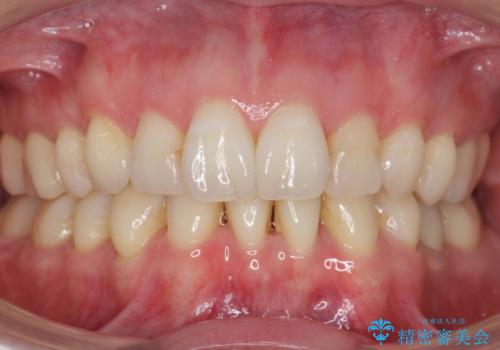

![[ 前歯のねじれ・がたつき ] マウスピース矯正の症例 治療後](https://seimitsushinbi.jp/wp/wp-content/uploads/2024/02/e7a01485e4f4dd0da04705fde4cc34cc-500x350.jpg?v=1708502585)